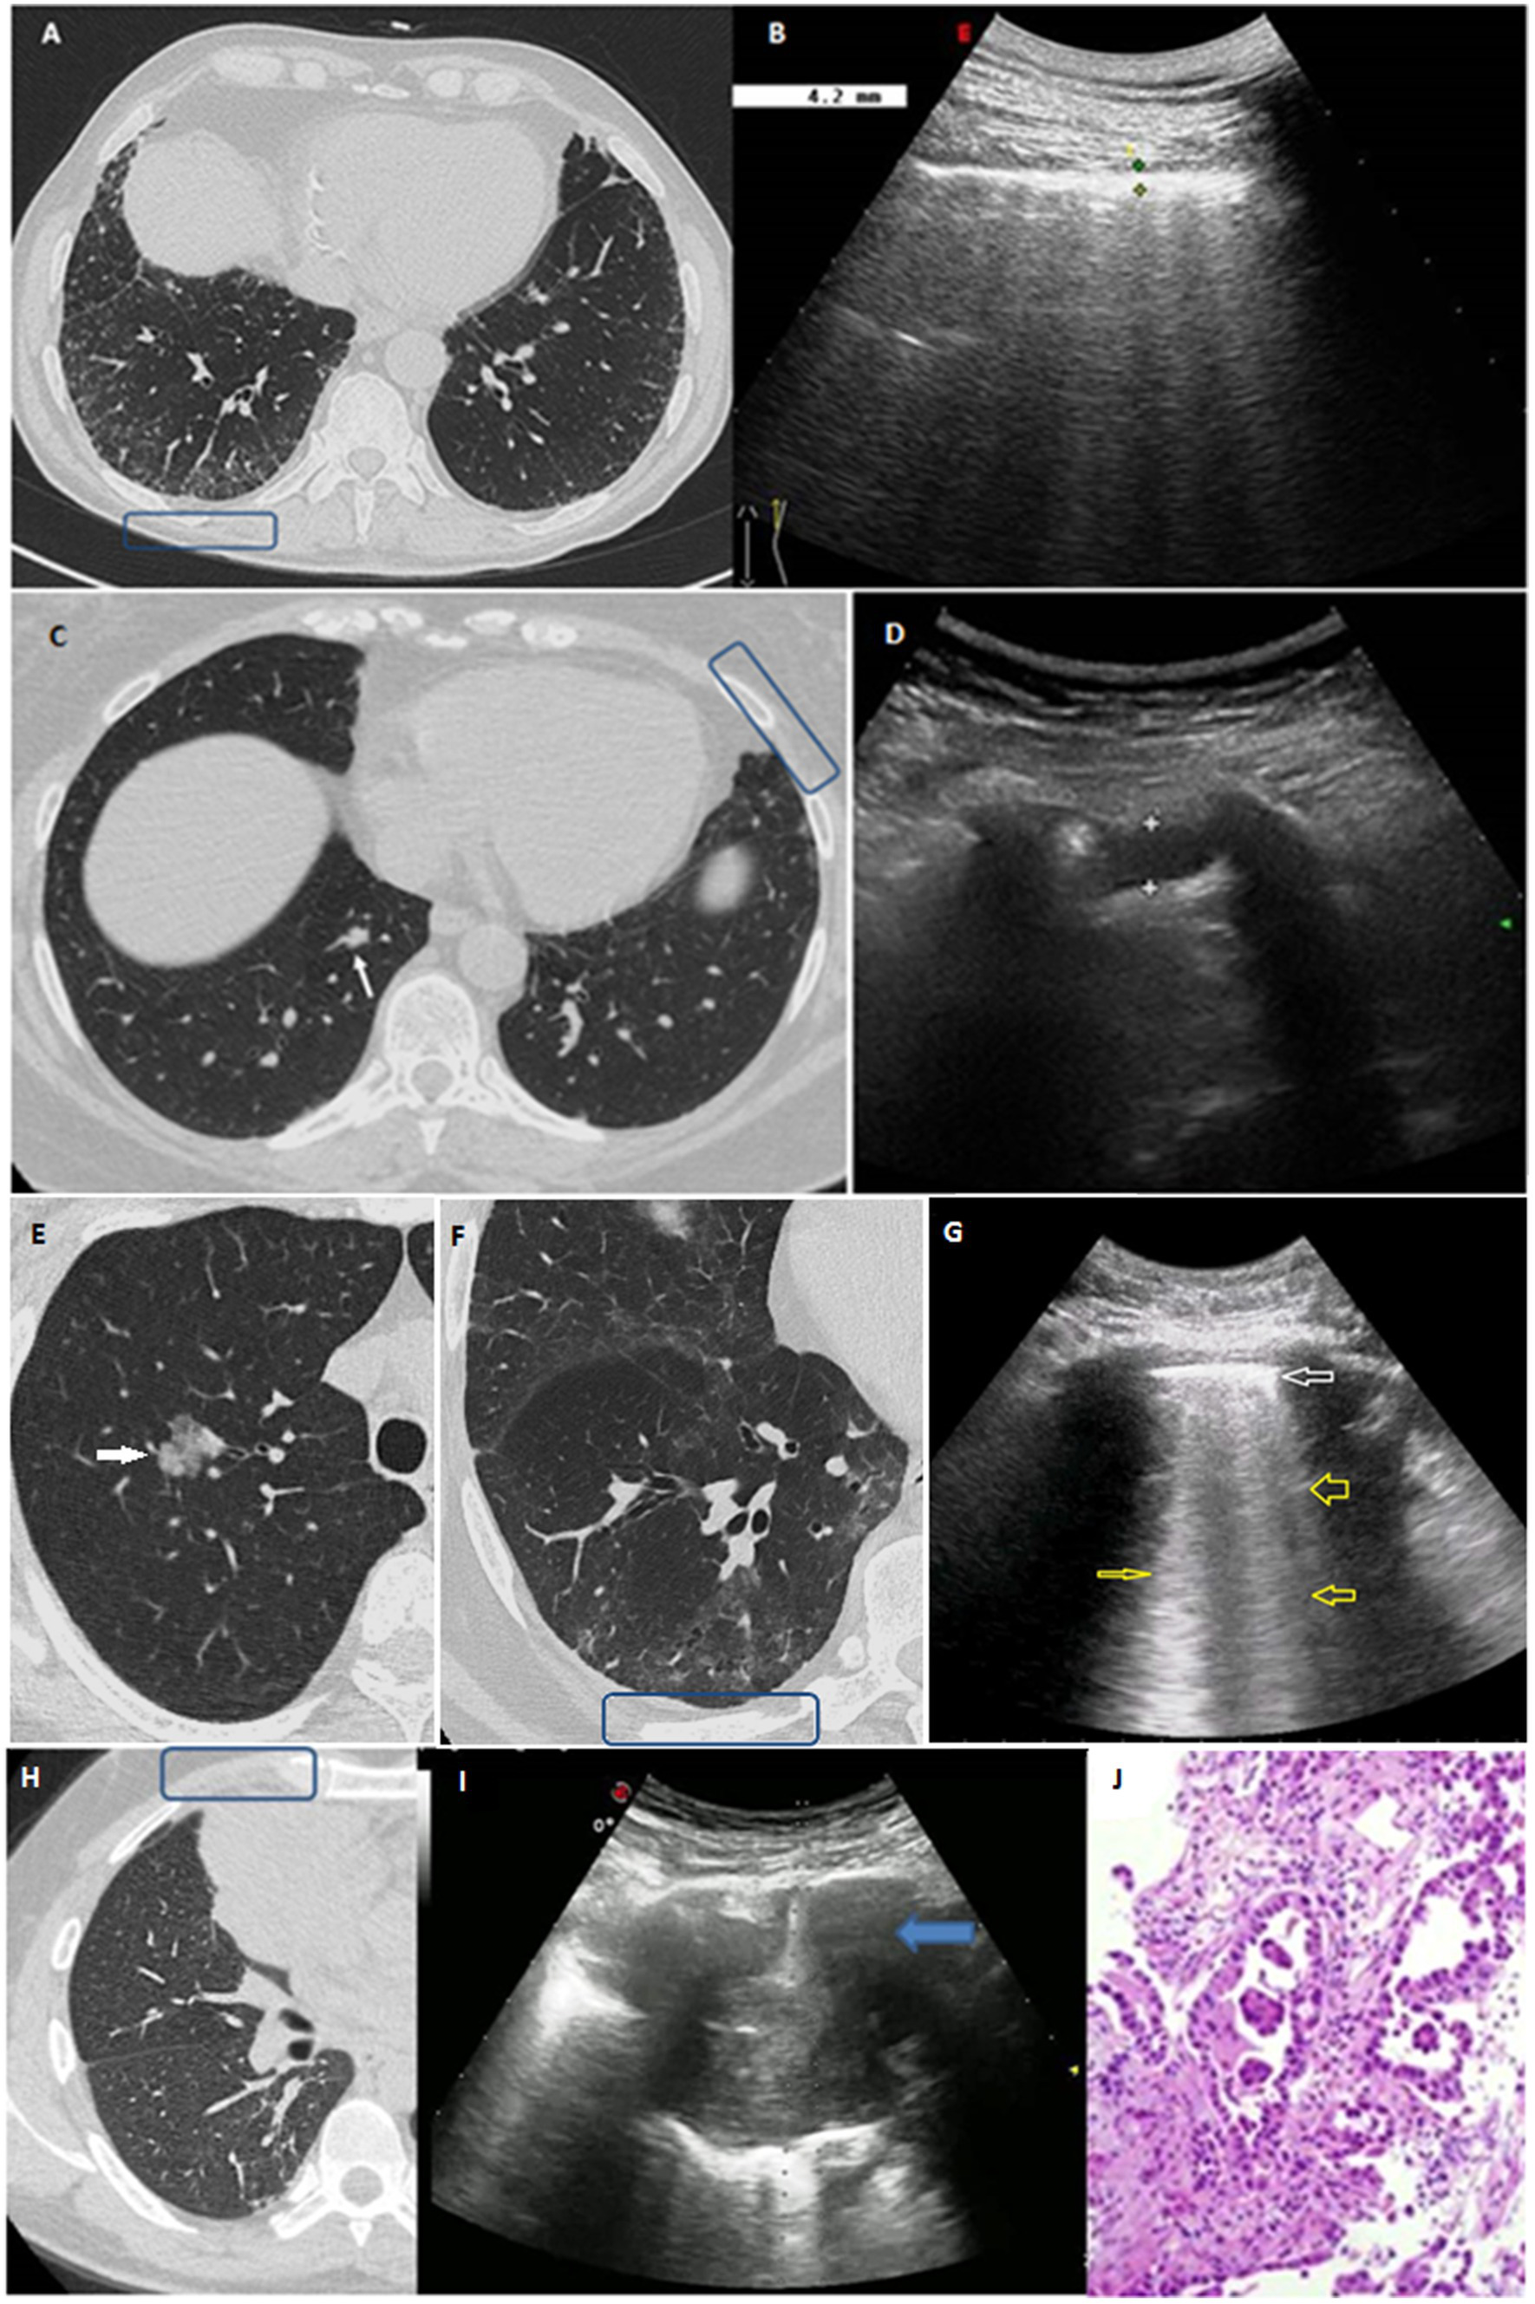

Figure 2

(A,B) Clinical case 1: (A) HRCT scan displaying bilateral GGOs and superimposed reticular opacities in the subpleural regions of both lower lobes, especially on the right (blue box). (B) The corresponding TUS examination at the level of right posterior para-vertebral lower scan showed a thickened hyperechoic pleural line. (C,D) Clinical case 2: (C) Axial HRCT scan showing a subtle focal pleural thickening in the left lung (blue box) and an intraparechymal irregular solid nodule in the right lower lobe (white arrow). (D) TUS examination at the level of left anterior hemi-clavicular middle scan showed a hypoechoic stria. (E–G) Clinical case 3: (E) Axial HRCT scan showing the presence of a 21 mm intraparenchymal part-solid nodule in the right upper pulmonary lobe (white arrow) very suspicious for lung cancer. (F) Axial HRCT scan of the right lower lobe showing a subpleural area of GGO with subtle thickening of the intralobular septa and small traction bronchiolectasis indicative of parenchymal distortion (blue box). (G) TUS examination was not able to identify the nodule, but TUS scan at the level of right posterior para-vertebral lower zone assessed an irregular thickened hyperechoic pleural line (white arrow) with B line artifacts below (yellow arrows). (H–J) Clinical case 4: (H) HRCT scan showing the presence of a right lung mass in the middle lobe (blue box). (I) Ongoing TUS-guided biopsy at the level of the right anterior hemi-clavicular middle zone showed a lung consolidation. (J) The histological diagnosis was invasive lung adenocarcinoma.

A total of 36 patients (21.6%) presented interstitial abnormalities on HRCT scan. TUS was able to identify 34 participants presenting subpleural ILAs on HRCT scan, of whom 7 showed subpleural fibrotic ILAs (Figure 2, Clinical case 1:A–B). These subjects were referred to perform further pulmonological evaluation and, if necessary, subsequent HRCT scan to evaluate for progression. TUS was not able to detect interstitial abnormalities in 2 patients presenting non-subpleural interstitial thickening. Focusing TUS evaluation on the assessment of actual interstitial changes on HRCT, a thickened pleural line showed a sensitivity of 63.9% (48.2–79.6%) and a specificity of 69.5% (61.6–77.4%), hypoechoic striae showed a sensitivity of 38.9% (23.0–54.8%) and a specificity of 90.1% (85.0–95.2%), and subpleural nodules showed a sensitivity of 58.3% (42.2–74.4%) and a specificity of 77.1% (69.9–84.3%).

Next, we focused on the assessment of subpleural nodules. Forty six patients (27.5%) showed subpleural nodules on HRCT scan. The detection of subpleural nodules on TUS showed a sensitivity of 60.9% (46.8–75.0%) and a specificity of 81.0% (74.0–88.0%). In 24 patients (14.4%) HRCT scan revealed the presence of intraparenchymal nodules, which could not be directly imagined with TUS. Of them, 23 subjects presented a positive TUS examination for other findings. Patients with pulmonary nodules showing malignant features on HRCT scan were recommended to underwent further follow-up with low dose HRCT scan or with positron emission tomography/computed tomography (PET/CT) scan, according to the Fleischner Society’s guidelines (34). Following this evaluation, it was possible to make a diagnosis of lung cancer in 3 cases. Of them, 2 patients presented intraparenchymal nodules on HRCT scan and a TUS examination that was negative for subpleural nodules but positive for other findings (Figure 2, Clinical case 2:C–D and Clinical case 3:E–G). The remaining patient presented a big subpleural mass in the right lung that was possible to directly assess on TUS examination (Figure 2, Clinical case 4:H–J).